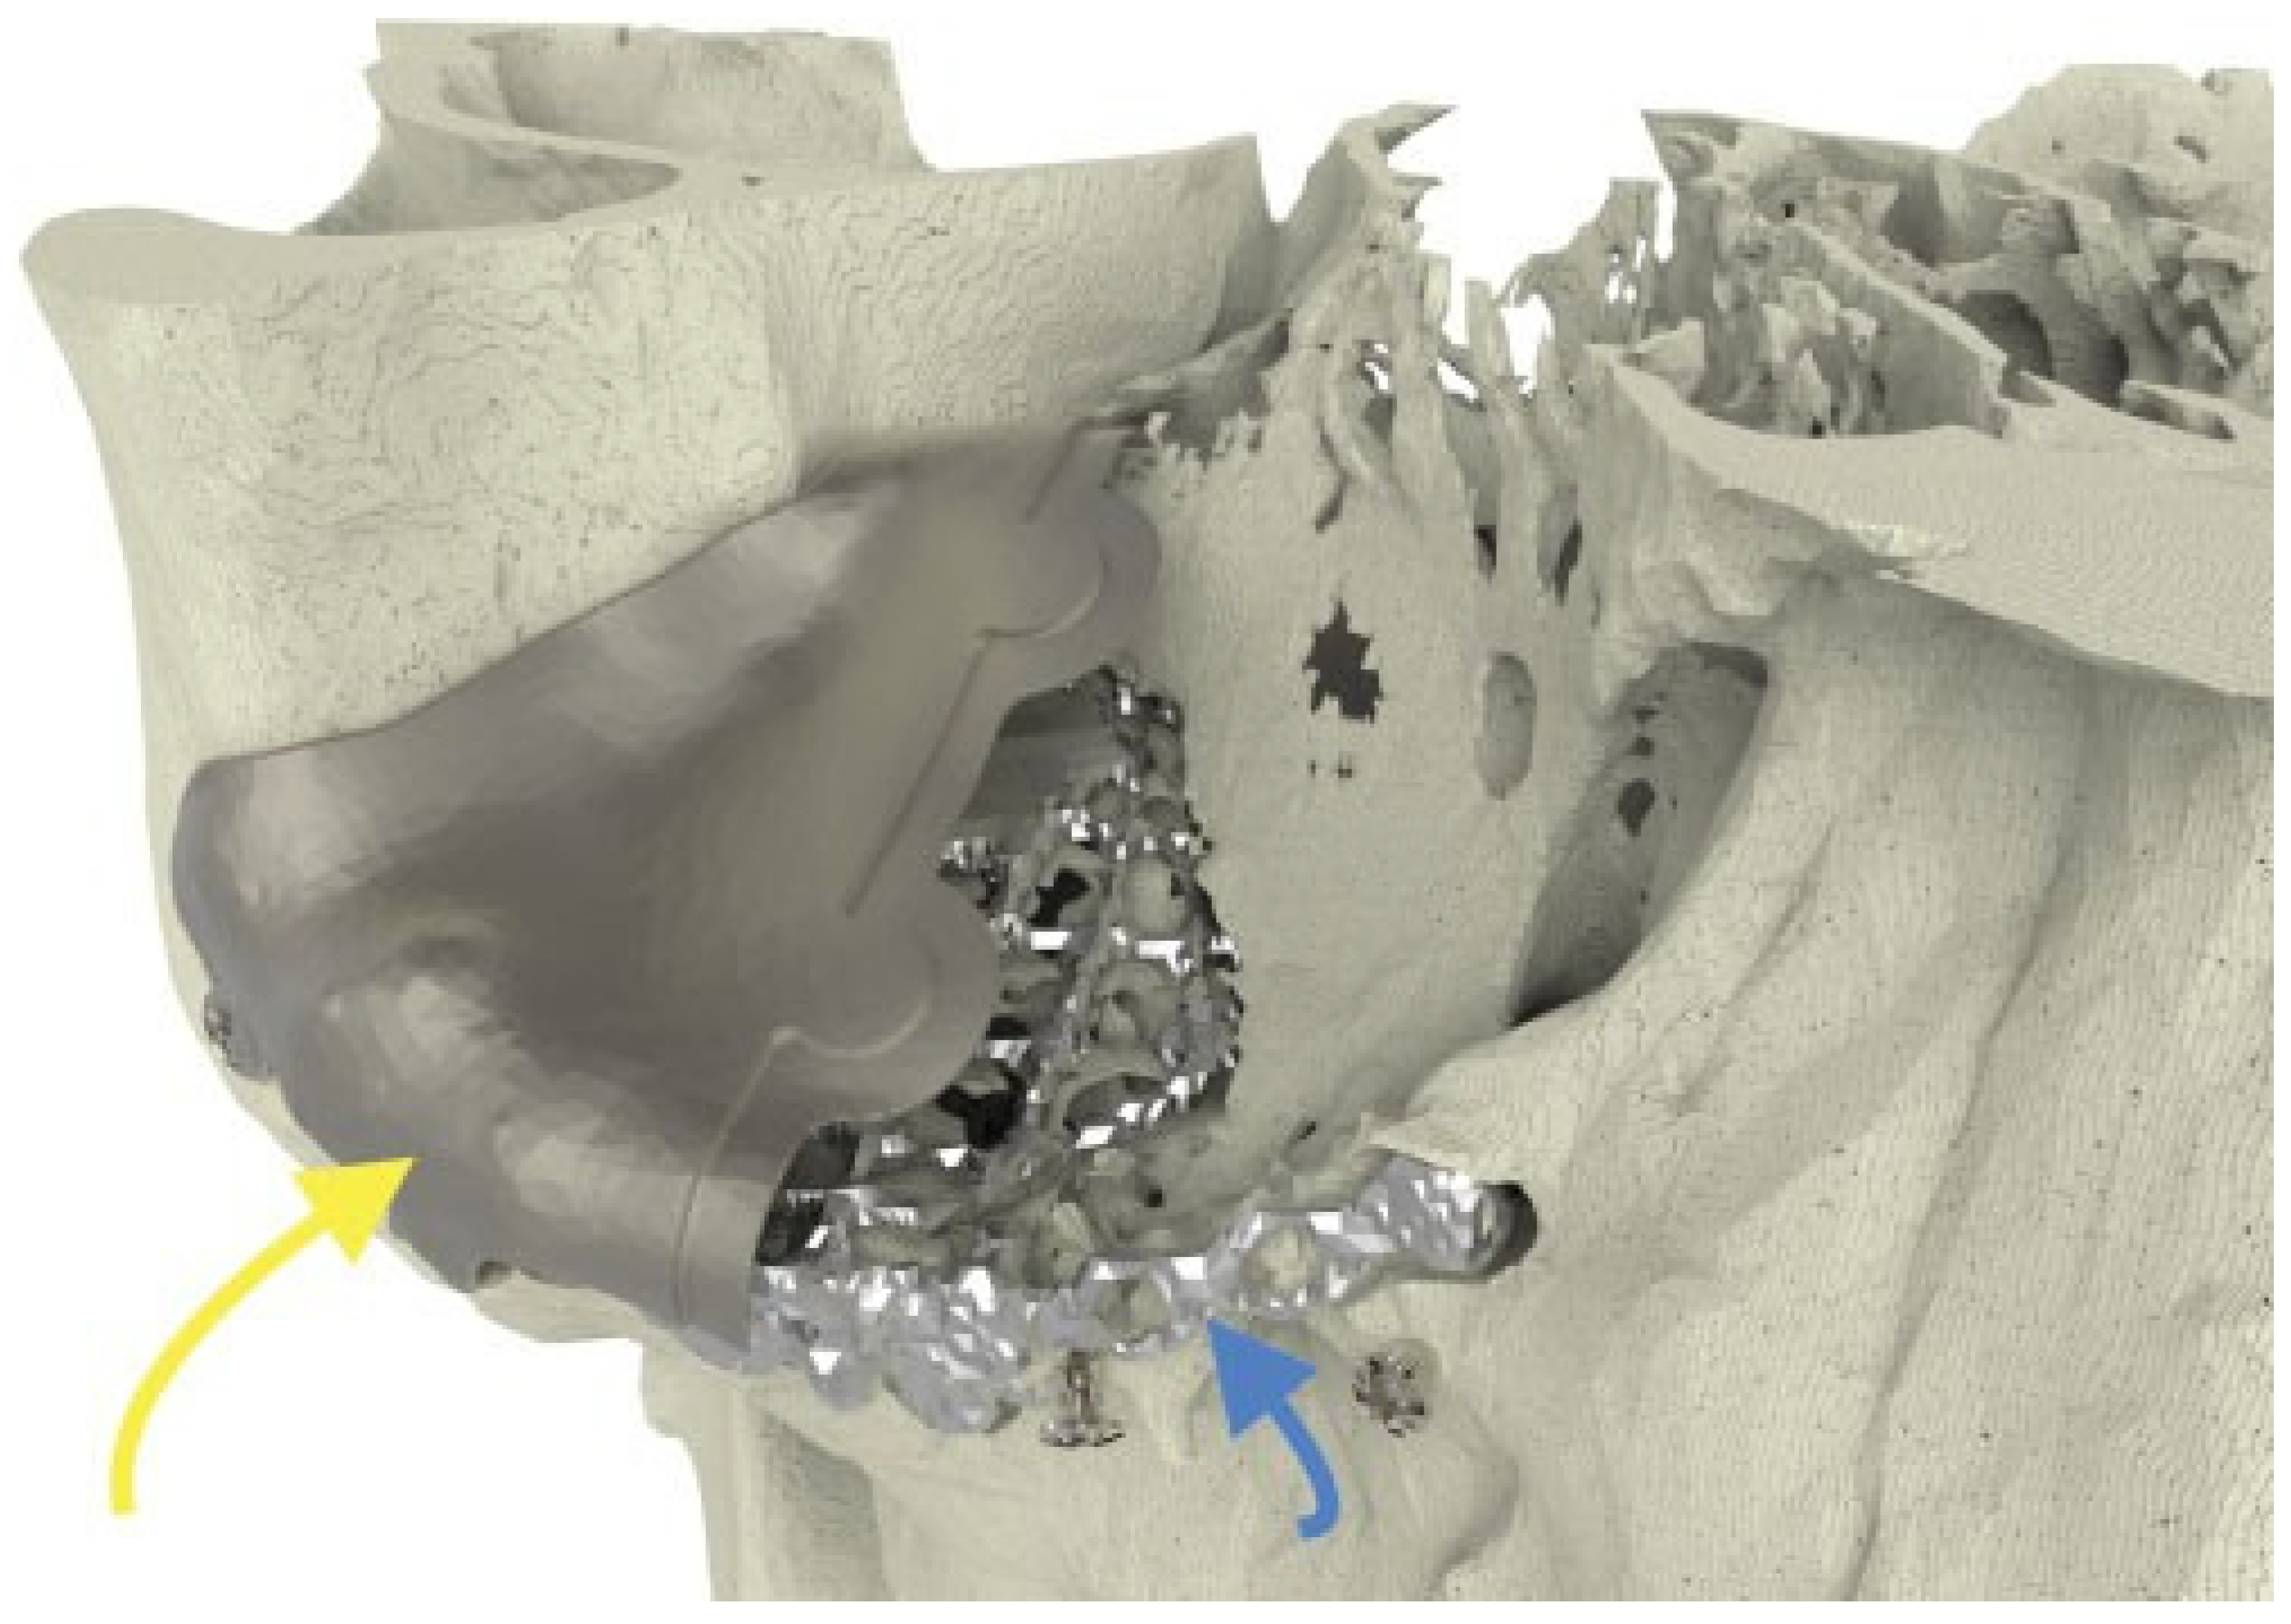

Figure 7. Case 2: Postoperative coronal CT scan, demonstrating nearperfect fit of the implant and symmetrical intraorbital content.